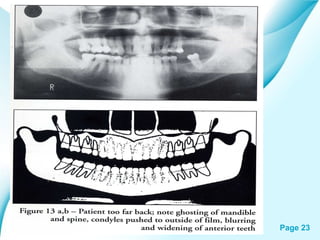

Powerpoint Templates

• 23.